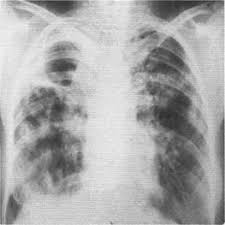

Яки з наведених рентгенограм відповідає спонтанному пневмотораксу.